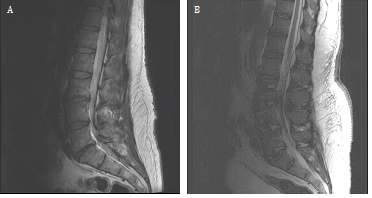

A 57 year-old male had lumbar stenosis and surgical correction with an anterior and posterior lumbar inter body fusion of L3-S1. After the surgery, his pain and strength improved and he was able to ambulate without his walker. Hethen presented to the emergency department nine days post-operatively with left leg paresthesias and weakness. His left leg was affected more significantly than his right, and he had difficulties with ambulation. Physical examination revealed weakness to 3/4 in the left leg and 4/5 in the right leg both proximally and distally. Reflexes were preserved in the arms and legs. Sensation was decreased in both legs to pin prick and he had a T12 sensory level. Over the next few days, he had further progressive leg weakness and then dropped reflexes. His workup included spine imaging which did not reveal any acute changes (Figure 1). Nerve conduction studies showed prolonged distal motor latencies, conduction blocks, as a well as sural sparing, consistent with a demyelinating polyneuropathy, specifically GBS. He was initiated on intravenous immunoglobulin (IVIG) therapy at a dose of 400mg/kg over five days. A lumbar puncture to assay CSF was not performed due to his post-lumbar surgical status and the confirmatory nature of the EMG. His sensory symptoms in his trunk fluctuated. There was also progressive cranial nerve involvement, with left facial weakness. He developed autonomic issues including urinary retention and atrial fibrillation, and was eventually incubated due to impending respiratory failure. The patient underwent a second cycle of a five day IVIG therapy course. Both weakness and sensation eventually improved. On first examination in the Emergency Department, GBS was not suspected as spinal level sensory involvement and asymmetric weakness with preserved reflexes is typically not characteristic of GBS. Additionally, because of his recent surgical history, his symptoms were thought to arise from possible post-surgical complications. The patient also did not have any antecedent infections. With the rapid progression of symptoms and then diminishing reflexes, GBS was then considered. Two months post-discharge, the patient began ambulating. His overall weakness has improved and has regained strength in his extremities. His only residual symptom is foot drop on the left. He is otherwise back to his baseline and had had return of his former excellent quality of life.

Figure 1 Magnetic resonance imaging of the lumbar spine.

A) Pre-operative sagittal T2-weighted image showing severe moderate lumbar stenosis at L3-L4, L4-5 and severe lumbar stenosis at L5-S1 levels.

B) Post-operative anterior and posterior lumbar interbody fusion of L3-S1 sagittal T2-weighted image showing reversal of cord compression.